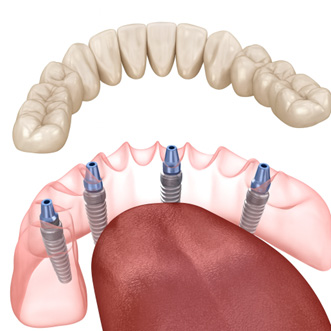

わずか4本のインプラントで、片顎すべての人工歯(フルアーチ)を支える固定式の治療法です。

従来の総入れ歯や多数のインプラント治療と比べて、手術負担を減らしつつ、しっかり噛める固定式の歯を短期間で実現できるのが特徴です。

| 支える本数 | 通常4本(骨の状態によりAll-on-6へ拡張も可) |

| 埋入角度 | 奥の2本を斜め(約30〜45°)に埋め込み、骨量を有効活用 |

| 固定方法 | 4本のインプラントに連結バーを介し、ブリッジ型の人工歯を固定 |